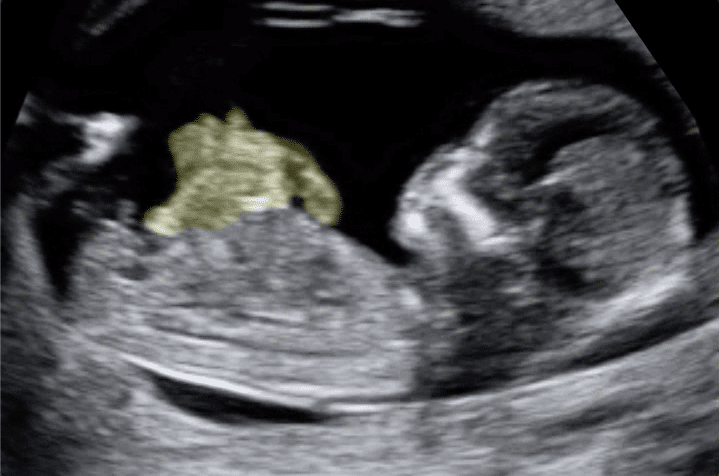

Encefalocele

A encefalocele é um defeito do tubo neural, doença na qual ocorre a herniação do cérebro e das meninges por aberturas